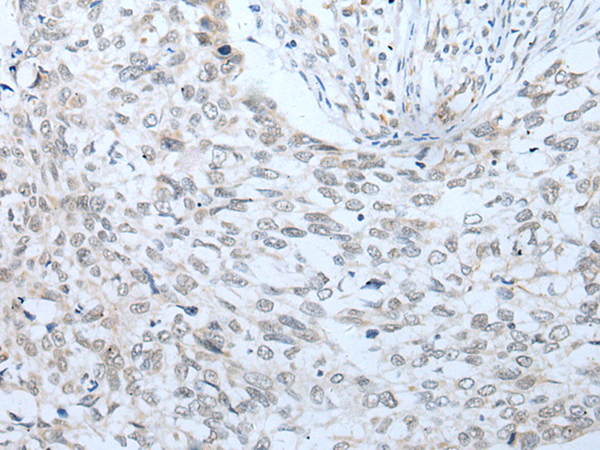

IHC positive control: |

Human lung cancer |

IHC Recommend dilution: |

20-100 |